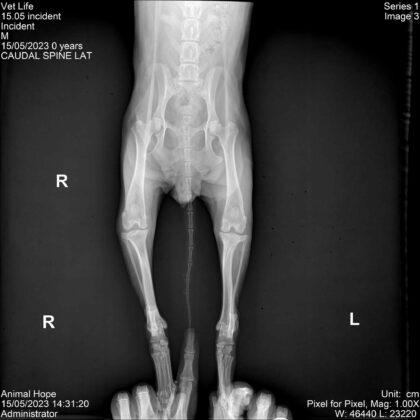

Животното е оцеляло, но е с парализирани задни крайници. Грижите за него са били поети от „Animal Hope Bulgaria – Burgas“, които са го транспортирали във варненска клиника, като по последна информация, то няма да проходи повече, но ще му бъде направена количка, с която да се придвижва. От организацията споделят:

„Оставяме баба Бубка в клиниката, където ще и бъдат направени отново кръвни изследвания, 4д тест, тест за Гана, катетаризираха я, защото задържа урина, започнаха веднага терапия за стабилизиране. След като я стабилизират, предстои операция на гръбнака за стабилизиране на прешлена. Най-вероятно няма да проходи сама повече, но ще живее и ще се придвижва с количка. На ден стационарът е 25 лева само престоя без включените медикаменти. Ще имам огромна нужда от вашата подкрепа. Може да ни подкрепите по един от следните начини: